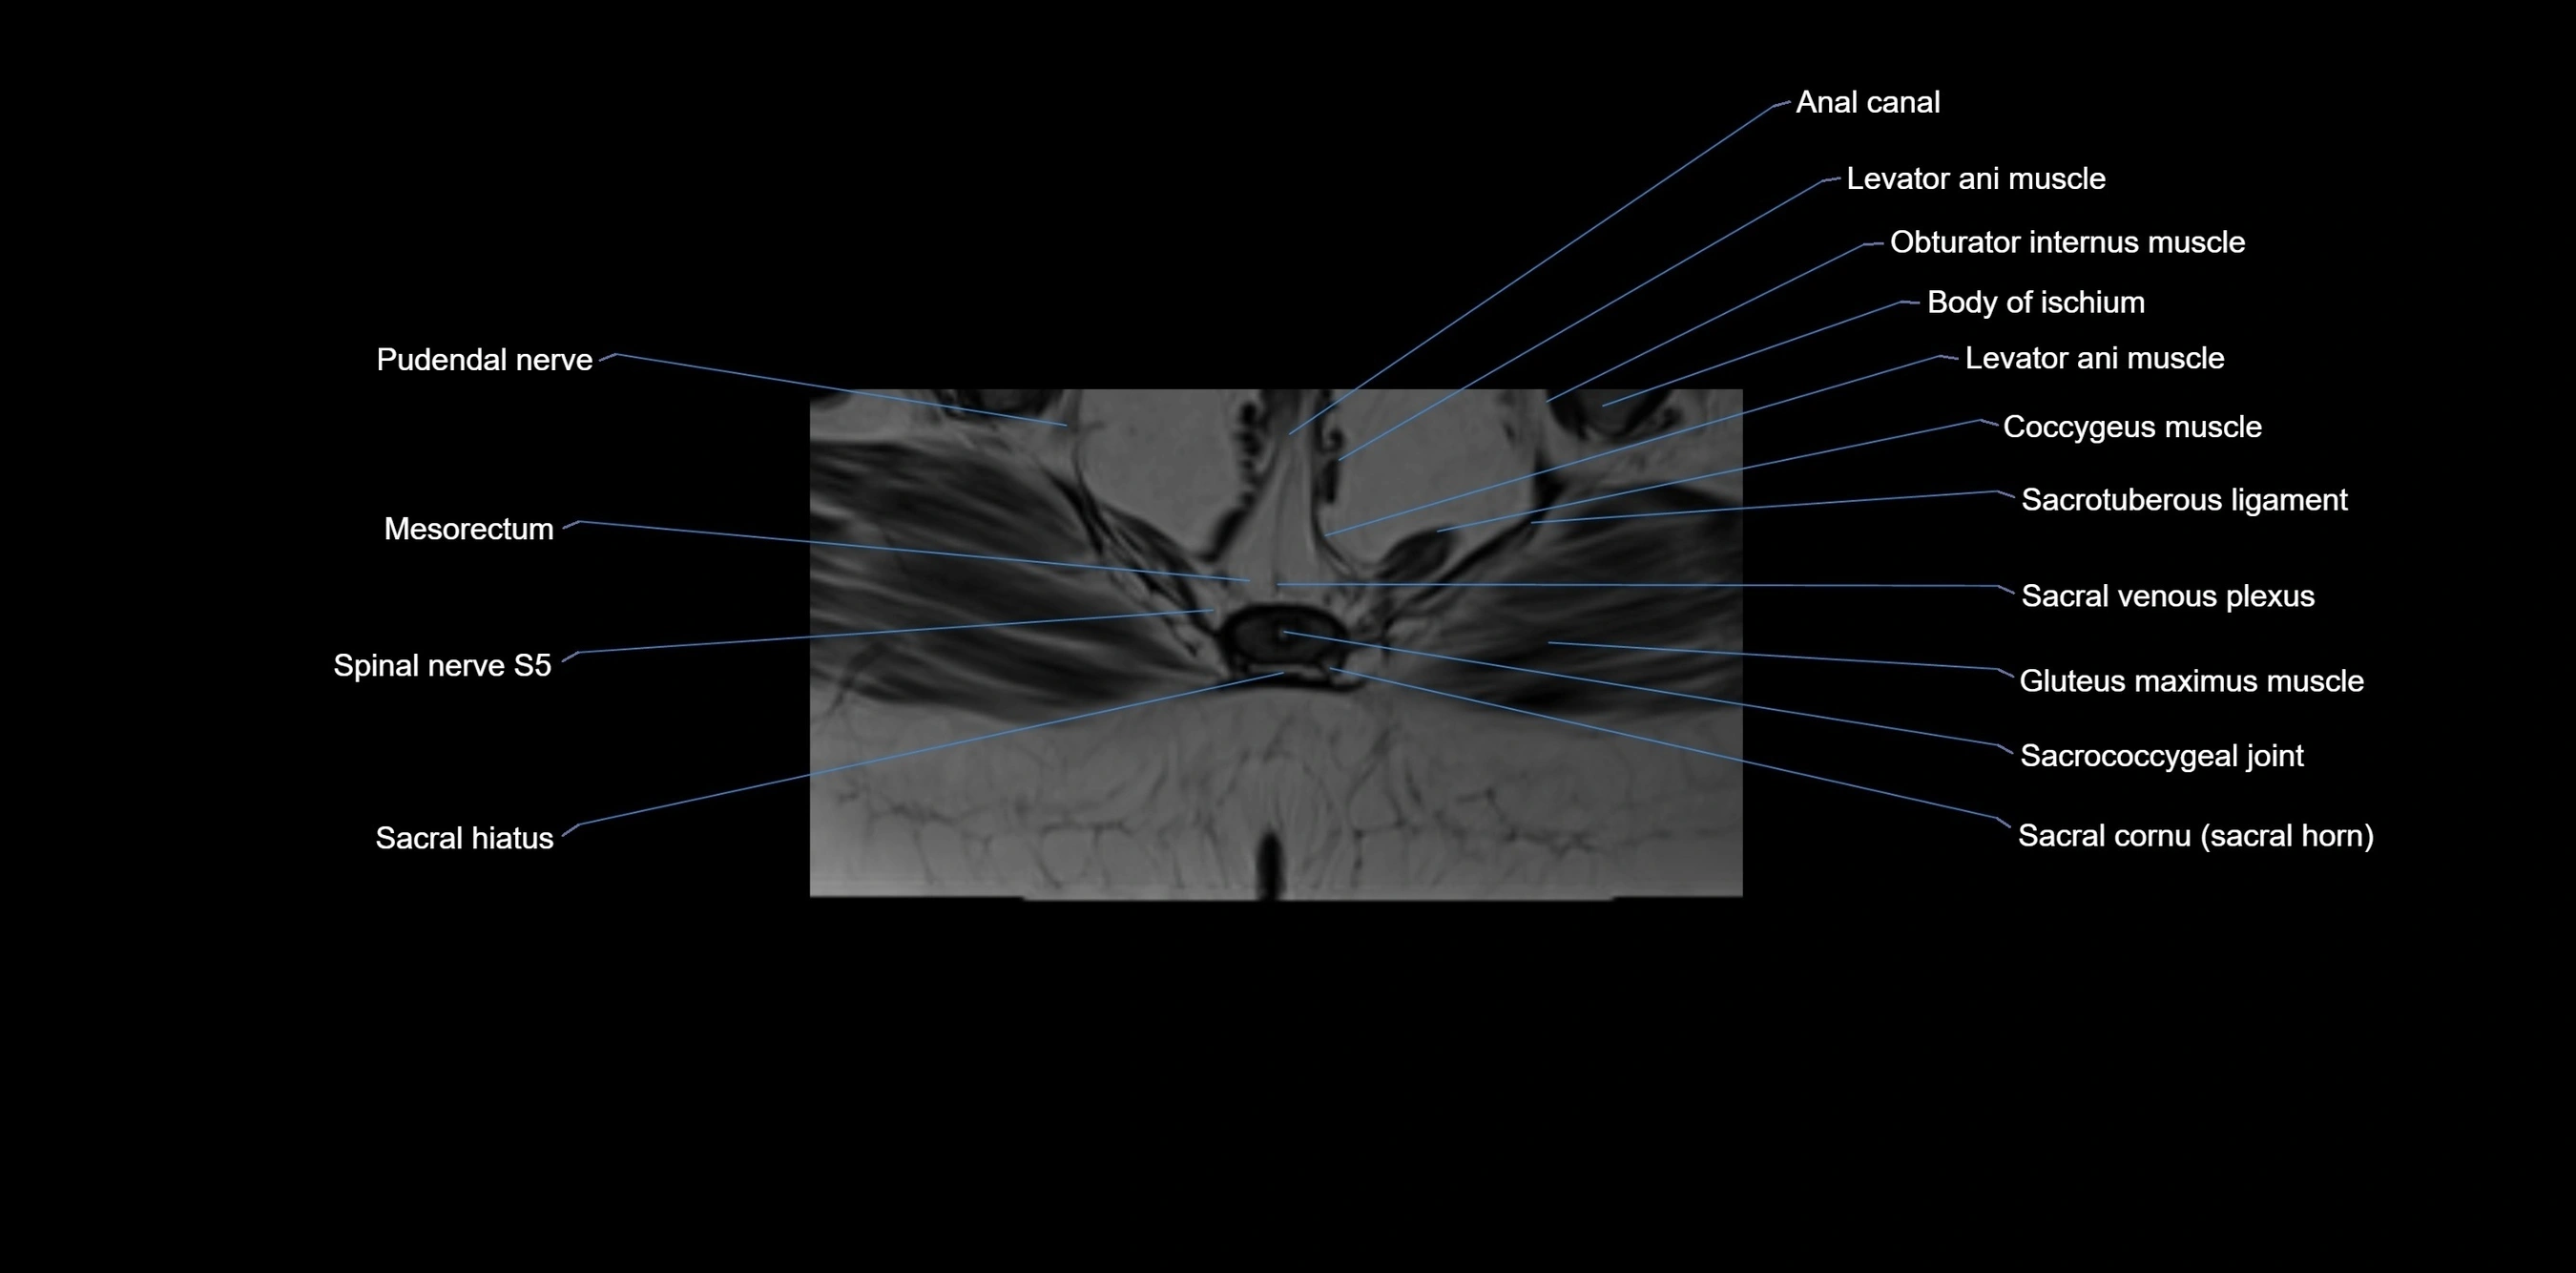

MRI Appearance

T1-weighted images:

• Cortical bone appears very low signal (dark); marrow shows intermediate signal

• Iliac fossa fat is bright against low-signal cortex

T2-weighted images:

• Cortical bone remains dark

• Marrow signal varies depending on fat content; edema or tumor shows hyperintensity

STIR:

• Suppresses fat, making bone marrow edema, fractures, or infiltrative lesions appear bright

• Excellent for trauma, sacroiliitis, and metastatic evaluation

T1 Fat-Saturated (Pre-contrast):

• Marrow: intermediate signal, fat suppressed

• Useful for detecting subtle marrow abnormalities adjacent to iliac cortex

T1 Fat-Saturated Post-Contrast (Gadolinium):

• Enhances vascularized structures, marrow pathology, tumors, and inflammatory changes

• Highlights soft tissue or bone invasion in pelvic neoplasms

MRI Non-Contrast 3D Imaging:

• Provides 3D morphology of iliac wing, crest, and articulations

• Used in preoperative planning for pelvic surgery and trauma reconstruction

MRI image

image